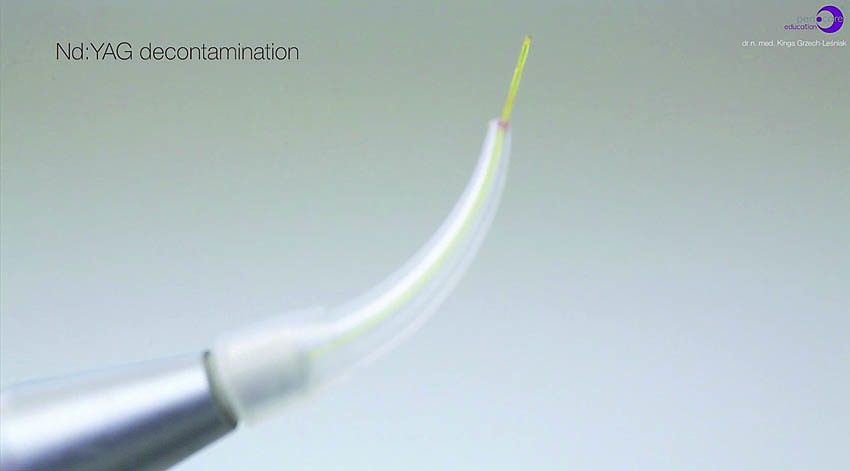

Πριν τη θεραπεία, η ασθενής υποβλήθηκε σε διαδικασία υποουλικού καθαρισμού με ξέστρα υπερήχων. Μετά τον καθαρισμό, η κλινική κατάσταση της ασθενούς βελτιώθηκε. Στη συνέχεια, εφαρμόστηκε ένα laser Nd:YAG για την αποστείρωση και την απολύμανση των περιοδοντικών θυλάκων (Εικ. 3 έως 7) και laser Er:YAG για την απομάκρυνση της υποουλικής τρυγίας (Εικ. 8 έως 12).